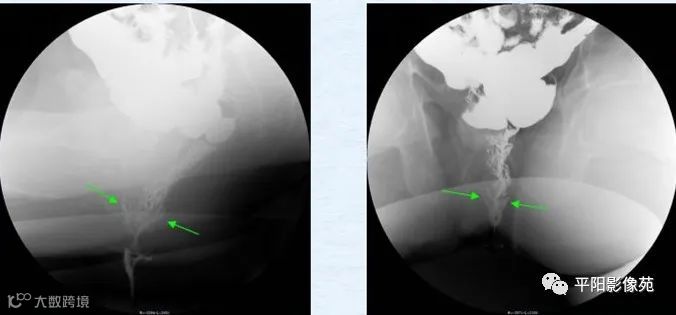

盆底痉挛综合征(spastic pelvic floor syndrome,SPFS):指用力排粪时盆底肌肉痉挛收缩而不松弛的功能性疾病。排便造影表现为力排时肛直角不增大,仍保持在90°左右或更小,且多出现耻骨直肠肌痉挛压迹(PRMI),即可诊断本病。合并直肠膨出时100%出现“鹅征”:即将力排片竖摆显示:直肠膨出为“鹅头”,肛管为“鹅嘴”,变细的直肠远段为“鹅颈”,直肠近段和乙状结肠为“鹅身”,宛如一只鹅,称为“鹅征”。(图 6,图7)

图6 力排相肛直角小于90°,钡剂排不出,直肠前缘突出,局部形态近似“鹅头”